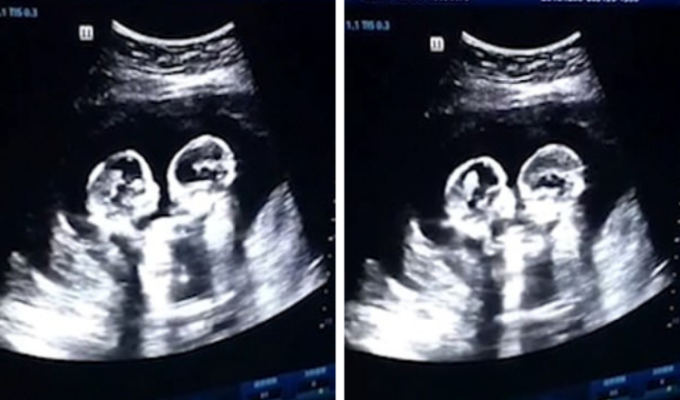

Guerra de bebés. El video de una ecografía a dos fetos ''peleándose'' en el útero de su madre dejó sorprendido a los médicos chinos, pero sobretodo a Teo, padre de las pequeñas.

Según comentó el hombre de 28 años al medio chino Chian Mail, en el último examen se sintió sorprendido de ver ''pelear'' a sus dos hijas antes de nacer: ''Parecía que estaban boxeando'', señaló.

''Nos emocionó mucho. Las bebés eran tan pequeñas y ya sabían cómo cuidar la una de la otra. Creo que vivirán en armonía cuando crezcan'', agregó.

El progenitor temía que sus hijas tuviesen problemas al nacer, debido a que compartían el mismo saco amniótico y placenta. Sin embargo, el ginecólogo He Lin, le aseguró que todo estaba en orden, por lo que su esposa no correría peligro durante la última fase del embarazo.